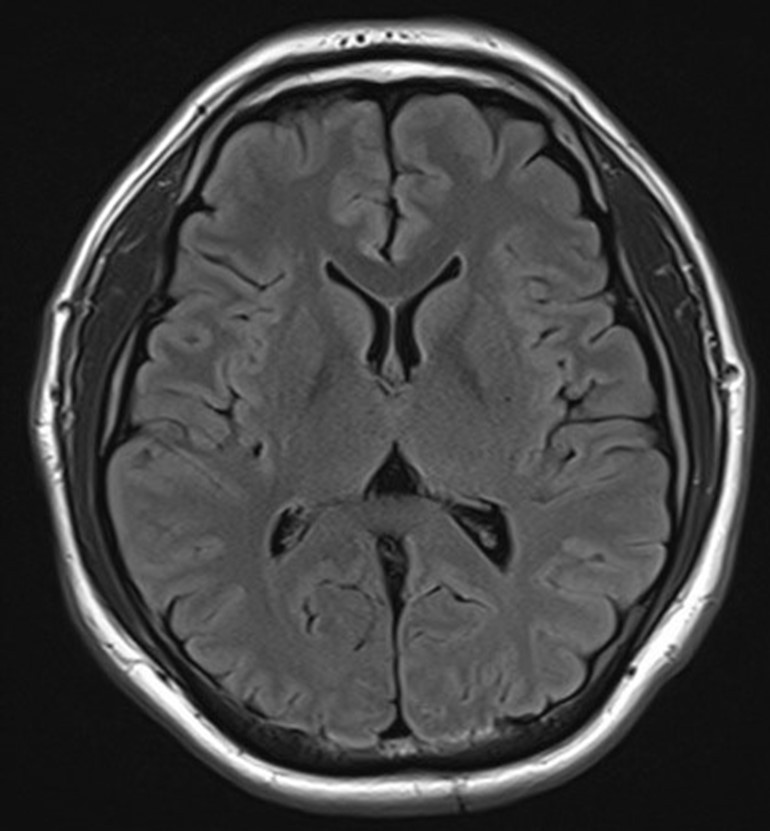

그림10.jpg 촬영 일시: 2025.05.09

<Fig 1. 정상 소견의 뇌 MRI>

MRI 결과가 나왔는데

예상대로 뇌는 정상이었어요.

환자분께 뇌에는 아무 이상이 없다고 말씀드리니

일단은 안도하시더라고요.

그런데 여기서 멈추면 안 되죠.